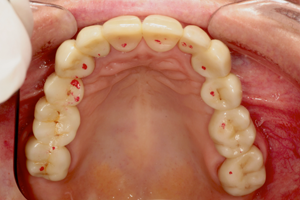

In deze lezing wordt dieper ingegaan op de verschillende stappen bij het plaatsen van de enkelvoudige posterieure composietrestauratie: de keuze van het composiet en adhesief systeem, de caviteitspreparatie, afzondering, het matrixsysteem, laagjes techniek versus bulk fill, vormgeving, occlusie en afwerking. Zowel de meer beperkte als uitgebreide posterieure composietrestauratie met knobbelopbouw komen aan bod. Tenslotte wordt belicht dat regelmatig onderhoud en lokaal herstel van de defecte posterieure composietrestauratie de levensduur zal verlengen.

Voorspelbare functie en esthetiek van de definitieve restauratie bij patiënten met een (ernstig) versleten dentitie vereist een gezamenlijke klinische en technische benadering door tandarts en tandtechnicus. Een systematisch concept bereik je door nauwkeurige behandelplanning met een diagnostische wax-up waarmee materiaalkeuze, preparatievorm, ‘soft-tissue management’ en tijdelijke voorzieningen worden bepaald. Tijdelijke voorzieningen spelen een essentiële rol in de communicatie tussen de patiënt en het behandelteam.

Tijdens deze lezing komen de volgende aspecten aan de orde: Esthetische en functionele analyse, behandelplanning, teamwork, materiaalselectie, CAD/CAM techniek, digitale beetbepaling, 3D gezichtsscan, moderne hoog-gevulde polymeren en volkeramiek.